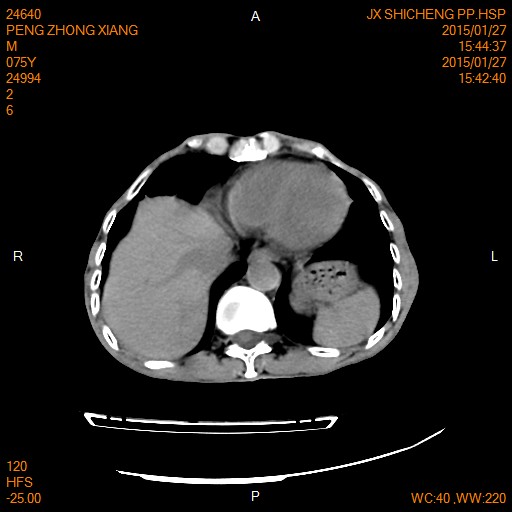

CT49858:右下腹部肿块,性质?

男性,75岁。发现右下腹部包块一周。

1、右侧结肠癌。

2、胆囊结石伴慢性胆囊炎。

1、考虑炎性包块。

2、胆总管扩张。

病变位于肝十二指肠韧带内及肝下间隙内,延迟持续强化,并见环形强化,另间隙内见无强化液体,有条索状影,肾周筋膜增厚。从病变及周围改变来看倾向于炎性包块(含炎性肉芽组织),这个部位炎性包块以上消化道穿孔多见,顶部见一小气泡是肠内还是肠外不好确定。

结肠癌或间质瘤